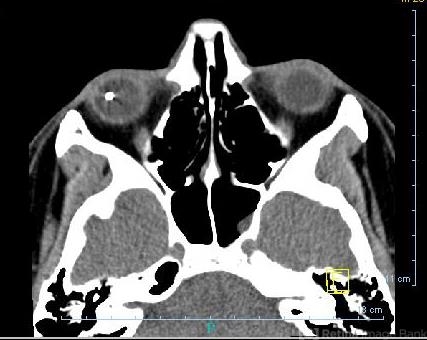

- CT scan

- Axial CT scan showing right metallic intraocular foreign body.